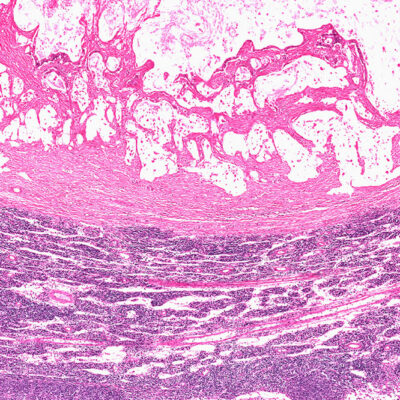

Heart diseases are one of the top reasons for death all over the world. Heart diseases are caused to a person due to many reasons. But, a major reason, which always causes a heart disease, is a high level of cholesterol in the blood. Yes, the different levels of cholesterol in the blood are also responsible for causing diseases, which are directly related to the heart.